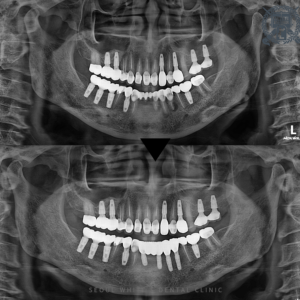

영도치과, 치주질환과 오래된 보철로 무너진 치아 전악 임플란트로! 안녕하세요! 영도치과 서울화이트S치과 입니다! 이전에 치과에서 보철치료를 많이 하셨거나 단 한개라도 보철물 장착으로 마무리 하신 분들께 영도치과 서울화이트S치과에서 드리는 말씀이…

영도치과, 전체적으로 나빠진 치아들 나에게 맞는 임플란트로 회복! 안녕하세요! 영도치과 서울화이트S치과 입니다! 치과로 내원해주시는 환자분들 중에서 안타까운 마음이 드는 분들이 계신데요. 오랜기간동안 바쁜 일상으로 구강관리를 소홀히하여 아프고…